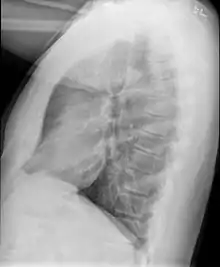

Example of early disease with mild flattening of the diaphragm

Bronchiolitis obliterans is often diagnosed based on the symptoms of obstructive lung disease following lung injury. The definitive diagnosis is through biopsy, but due to the variable distribution of lesions, leading to falsely negative tests, and invasive nature of this procedure it is often not performed.[6][11] Several tests are often needed to diagnose bronchiolitis obliterans, including spirometry, diffusing capacity of the lung tests (DLCO), lung volume tests, chest X-rays, high-resolution CT (HRCT), and lung biopsy.[11][4]